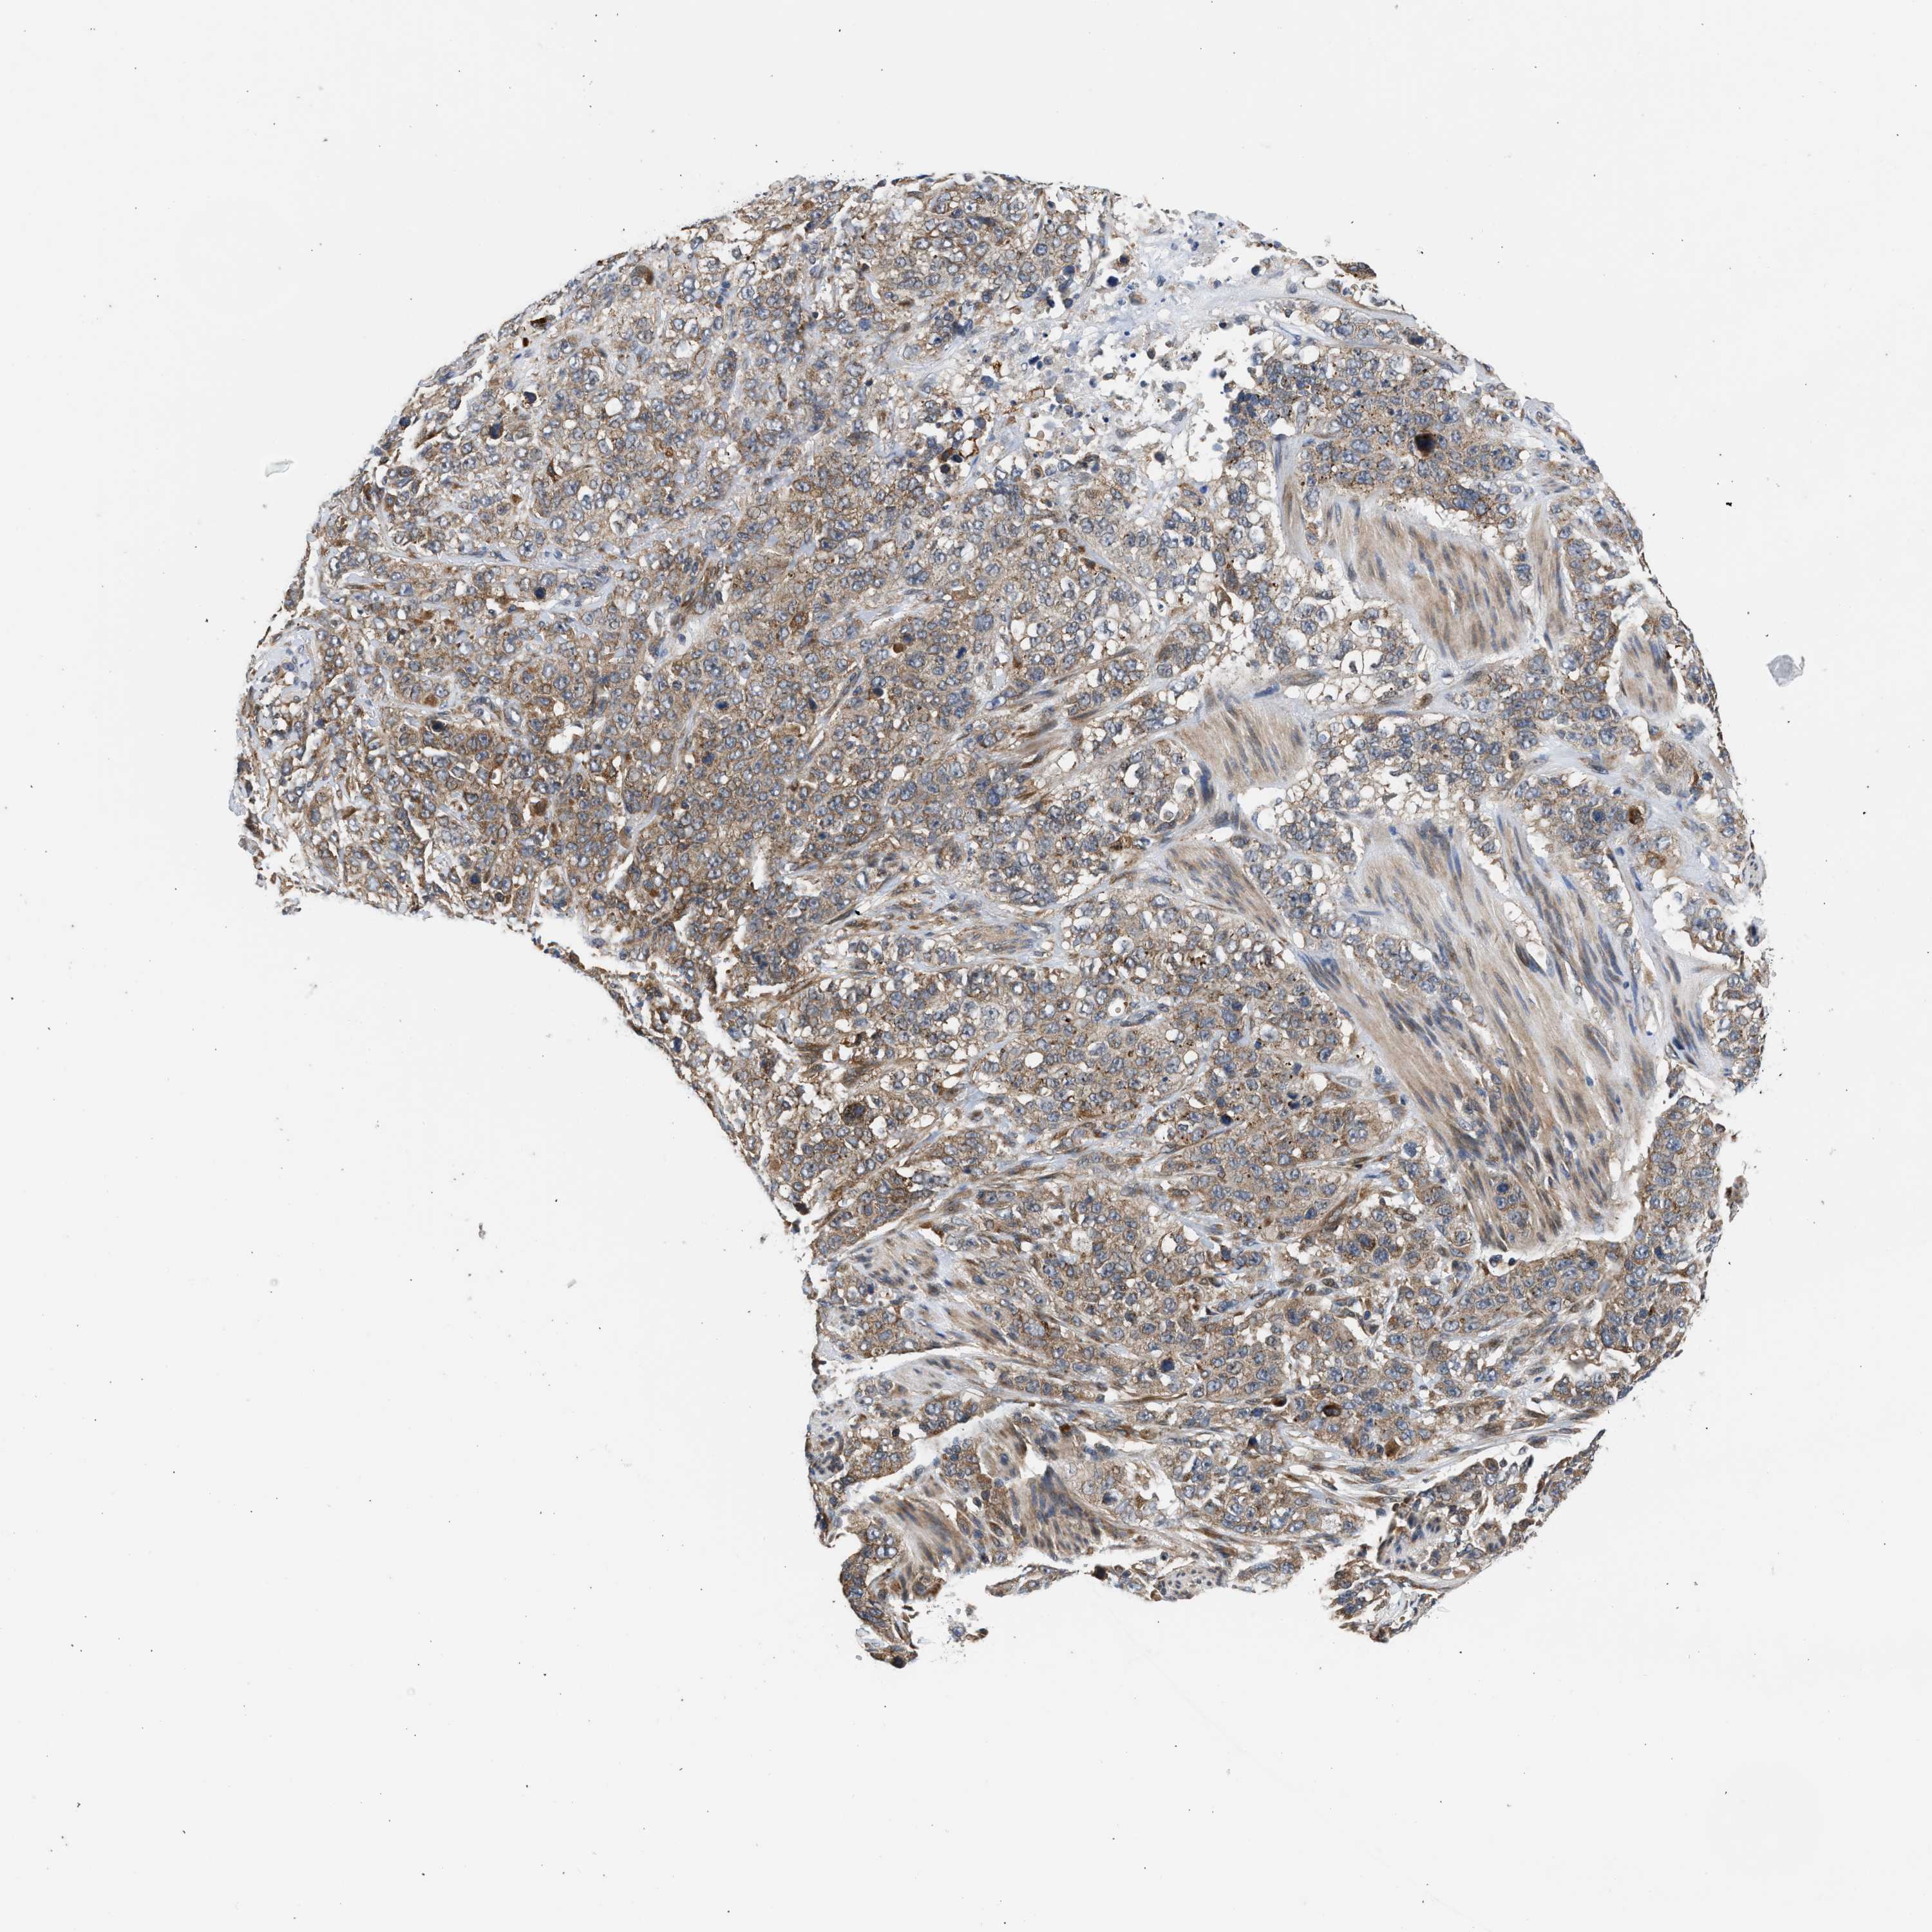

STOMACH CANCER - Protein expressioni

A mouse-over function shows sample information and annotation data. Click on an image to view it in a full screen mode. Samples can be filtered based on level of antibody staining by selecting one or several of the following categories: high, medium, low and not detected. The assay and annotation is described here.

Note that samples used for immunohistochemistry by the Human Protein Atlas do not correspond to samples in the TCGA dataset.

Antibody stainingi

Antibody staining in the annotated cell types in the current human tissue is reported as not detected, low, medium, or high, based on conventional immunohistochemistry profiling in selected tissues. This score is based on the combination of the staining intensity and fraction of stained cells.

Each image is clickable and will lead to virtual microscopy that enables deeper exploration of all samples and also displays staining intensity scores, fraction scores and subcellular localization as well as patient and tissue information for each sample.

Antibody HPA023202

Antibody CAB017030

Staining

High

Medium

Low

Not detected

Intensity

Strong

Moderate

Weak

Negative

Quantity

>75%

75%-25%

<25%

None

Location

Nuclear

Cytoplasmic/membranous

Cytoplasmic/membranous,nuclear

Adenocarcinoma, NOS

Adenocarcinoma, High grade